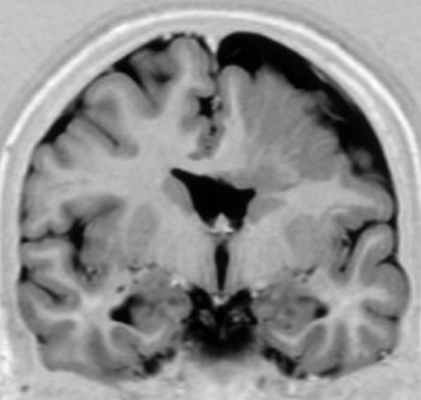

МРТ. Т1-зависимая корональная томограмма. Агирия.

Лиссэнцефалия – это общий термин, под которым понимают нарушение формирования борозд. Крайнее проявление ее – полное отсутствие извилин – агирия. Серое вещество имеется, но оно не разделено бороздами. Агирия может быть локальной, обычно этот тип наблюдается в височной доле.

Аномально малое число извилин в связи с неполными бороздами называется пахигирией. Обычно, она также локальная, извилины широкие и сглаженные. Сочетание участков пахигирии и агирии называют лиссэнцефалией I типа. При МРТ определяется утолщение коры, вертикальные Сильвиевы борозды и часто выпрямленные гиппокампы. Клинические проявления укладываются в различные формы (синдромы Миллера – Декера, Нормана – Робертса и т.д.), проявляющиеся в первый год жизни. Тип II отличается нарушением структуры самой коры, которая пронизана сосудами и фиброглиальными пучками. Этот тип сочетается с гидроцефалией и неполной миелинизацией. Характерно клиническое проявление в виде синдрома Уокера – Варбурга.

Диагноз типа I лиссэнцефалии стал возможным при помощи современных методов нейровизуализации. КТ и МРТ демонстрируют характерный внешний вид широкой кортикальной пластинки, с несколькими присутствующими или отсутствующими извилинами, отделенными от гиподенсивного белого вещества слегка волнистой или почти прямолинейной границей. Слоистость коры может быть выявлена при КТ или МРТ с высокой степенью разрешения. Патологические изменения обычно доминируют в задней части коры, в то время как несколько изгибов можно обнаружить спереди. При ультрасонографии уже с 18,5-25 недели определяется гладкость коры плода или новорожденного (Toi et al., 2004). МРТ дает более точные результаты (Ghai et al., 2006).

Классическая (тип I) лиссэнцефалия.

Т1-взвешенная аксиальная МРТ: (мутация LIS I) толстая корковая лента с гладкой поверхностью и прямой, неволнистой границей между серым и белым веществом.

Обратите внимание на присутствие нескольких мелких борозд в лобной области и полное отсутствие борозд сзади,

отсутствие оперкуляции с широко открытой сильвиевой бороздой и слоистость коры со слабой границей между гетеротопированными и полностью мигрировавшими нейронами.